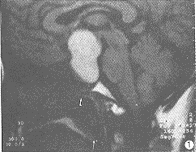

MRI信号特征:9例HPA瘤体在T1WI和T2WI均呈高信号。在T1WI上,6例呈均匀一致的高信号(图1),其余3例呈不均匀的高信号。1例表现散在点状高信号,1例瘤体中心高信号(图2),1例瘤体上半部分高信号,下半部分等信号(图3),。1例EHF引起的垂体出血在T1WI和T2WI呈不均匀的高信号,Gd-DTPA后见血肿轮廓明显强化,肿胀垂体实质略有不均匀强化(图4)。1个月后复查,肿大垂体已明显缩小,大小0.6cm,信号均匀(图5)。

图1 HPA。T1WI矢状位,瘤体呈均匀高信号